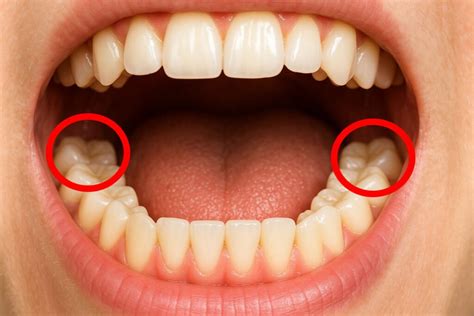

En la odontología moderna, la colocación de brackets dentales es una práctica común para corregir la alineación de los dientes y mejorar la salud bucal en general. Sin embargo, surge una pregunta frecuente entre quienes llevan brackets: ¿es posible extraer la muela del juicio mientras se llevan puestos los brackets? En este artículo, abordaremos esta interrogante con detalle y precisión.

La extracción de la muela del juicio con los brackets dentales colocados es una práctica que puede llevarse a cabo sin problemas en muchos casos. Según la recomendación del cirujano maxilofacial, esta intervención no está contraindicada y no suele presentar dificultades adicionales debido a la presencia de la aparatología ortodóncica.

La decisión de extraer las muelas del juicio (terceros molares) antes o después de la colocación de los brackets depende de varios factores, incluidos la posición de las muelas del juicio, el espacio en la boca, y el plan de tratamiento ortodóntico. Aquí hay algunas consideraciones importantes:

- Espacio y Alineación: Si las muelas del juicio están impactadas (es decir, no tienen suficiente espacio para erupcionar correctamente) o están causando problemas de alineación, puede ser recomendable extraerlas antes de comenzar el tratamiento ortodóntico. Esto ayuda a evitar que las muelas del juicio afecten la alineación de los dientes que los brackets están intentando corregir.